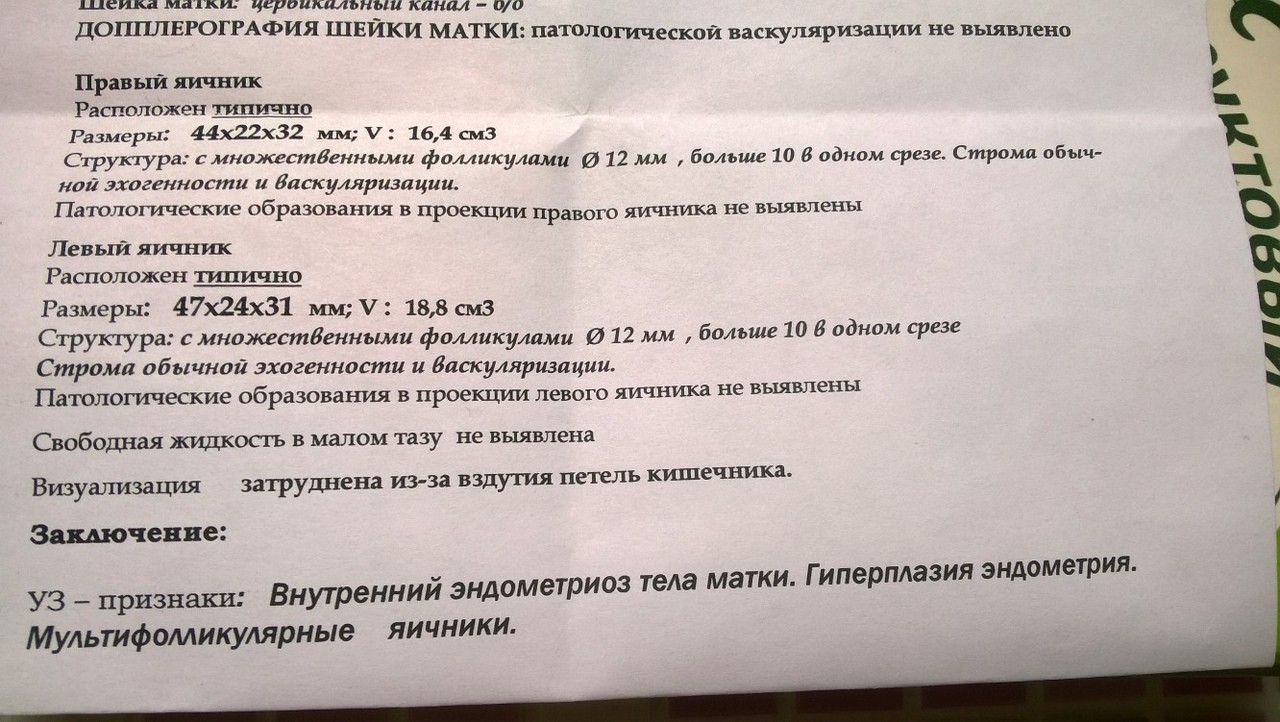

Медицинская диагностика: Гиперплазия эндометрия на УЗИ